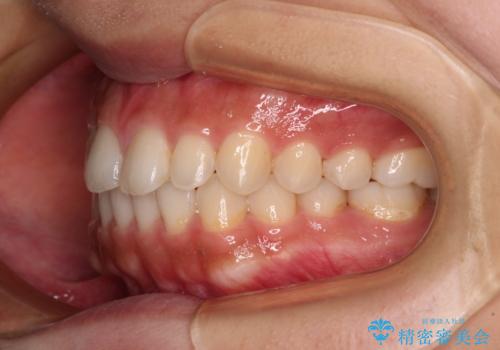

- インビザライン・ライト

- 1年5ヶ月

インビザライン・ライトは、製作できるアライナーの枚数に制限があるため、移動可能な量に限りがあります。

一方で、半年から1年程度で治療を終えることができるため、軽度の歯列不正の患者様には大変お勧めです。